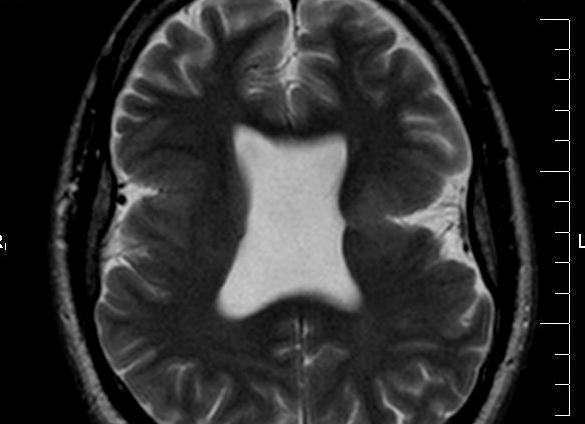

При подозрении на агенезию прозрачной перегородки и мозолистого тела выполняют МРТ.

Данный метод дополняет нейросонографию и позволяет выявить отсутствие перегородки, изменение структуры желудочков головного мозга. Магнитно-резонансная томография помогает определить характер поражения, отсутствие прозрачной перегородки и другие патологии, которые невозможно определить на УЗИ. Если агенезия частичная, то выявить патологию еще труднее.

Агенезия мозолистого тела при НСГ определяется широко расположенными в коронарной плоскости передними рогами боковых желудочков, полость прозрачной перегородки не визуализируется, нередко наблюдается расширение желудочковой системы. В сагиттальной плоскости отмечается нарушение расположения извилин: отсутствует поясная извилина, борозды отходят веерообразно. Окончательно мозолистое тело формируется после шести месяцев жизни, поэтому говорить о гипоплазии в периоде новорожденности не корректно.

Применение НСГ, КТ и МРТ позволило выделить следующие формы голопрозэнцефалии: алобарная, семилобарная, лобарная. При алобарной форме определяется единая полость вместо боковых и третьего желудочков; зрительные бугры не разделены; отсутствуют обонятельные луковицы, мозолистое тело и серповидный отросток мозговой оболочки. Алобарную форму необходимо дифференцировать с гидроанэнцефалией (отсутствие гемисфер мозга). Семилобарная форма характеризуется наличием одного желудочка, отмечается рудимент затылочных долей. Боковые желудочки сливаются в области передних рогов и тел, отсутствуют мозолистое тело и обонятельные луковицы, зрительные бугры могут быть частично разделены, третий желудочек гипоплазирован. При лобарной форме боковые желудочки соединены между собой на уровне передних рогов, отсутствует прозрачная перегородка, нижние и задние рога хорошо различимы, третий желудочек дифференцирован. Септооптическая форма голопрозэнцефалии, а также агенезия полости прозрачной перегородки при НСГ, КТ и МРТ имеют аналогичные лобарной голопрозэнцефалии характеристики.